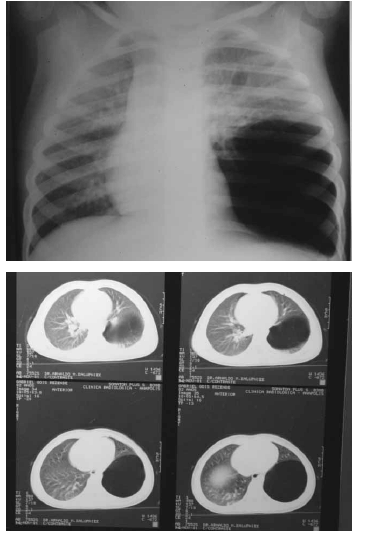

Um paciente de 6 anos de idade, com história de dispneia progressiva, principalmente após atividade física, apresenta tosse seca não incomodativa. Foi realizada radiografia de tórax seguida de tomografia, reproduzidas abaixo.

A respeito da situação apresentada, julgue os itens a seguir.